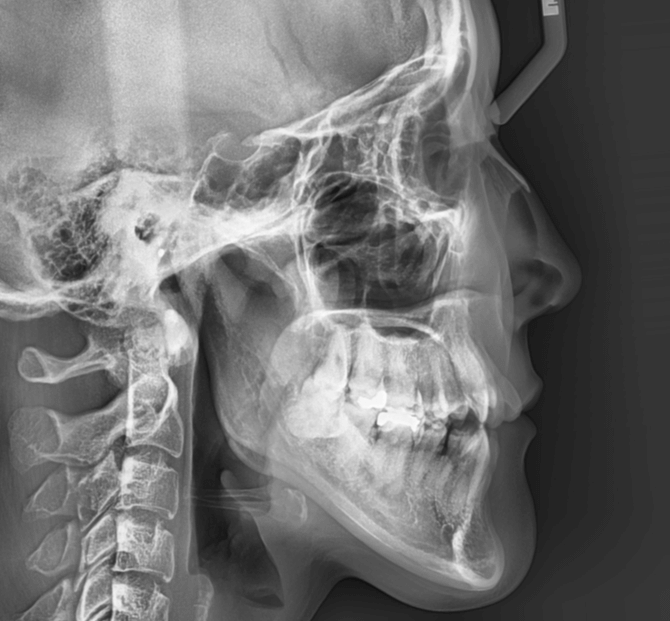

| 年齢・性別 | 15歳の女性 |

|---|---|

| 主訴 | 咬み合わせが逆であること(反対咬合)を気にされて来院された15歳7か月の女性。見た目や機能面の改善を希望されていました。 |

| 治療期間・回数 | 4年4ヶ月・28回 |

| 費用 | 900,000円 |